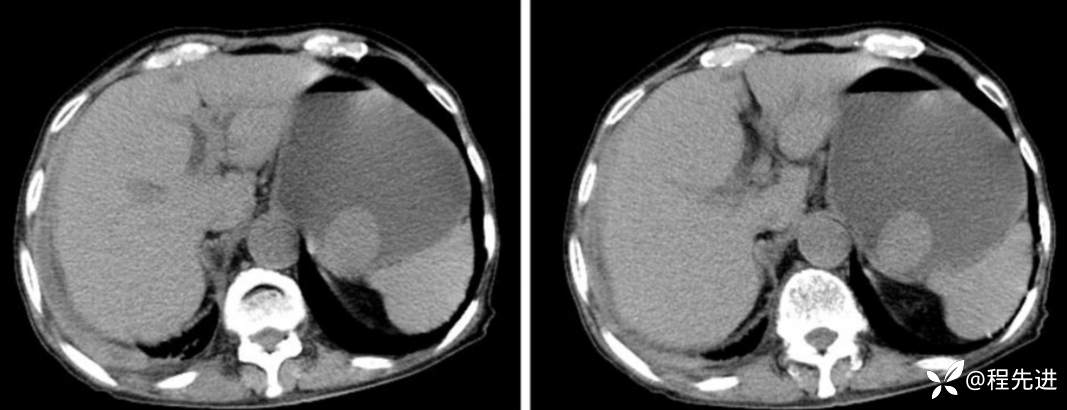

CT

门脉期